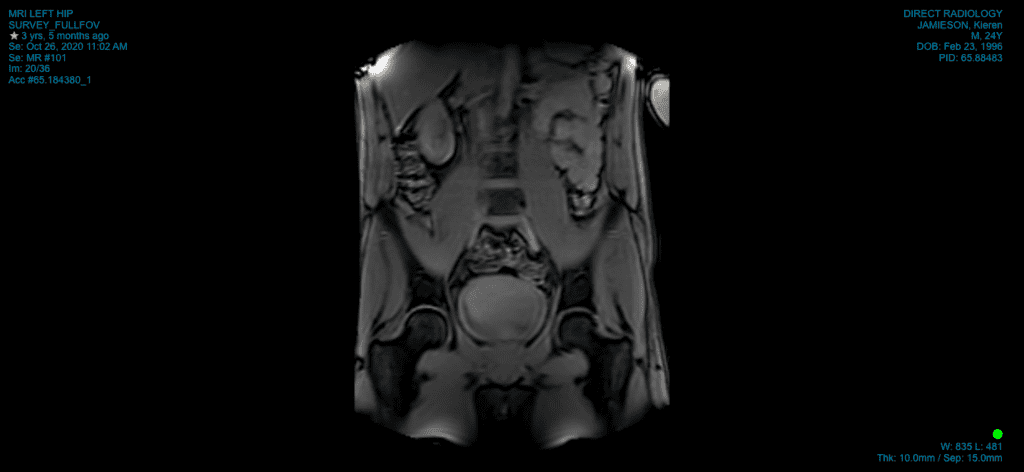

Upon seeking medical advice, I underwent consultations with various healthcare professionals, including student osteopaths, physiotherapists, sports doctors, and orthopaedic surgeons. The diagnosis of femoroacetabular impingement (FAI), labral tear, subchondral cyst and articular cartilage damage prompted discussions of surgical intervention, alongside cortisone injections and rehabilitative measures.

In my research, I stumbled upon a startling revelation: up to 60% of asymptomatic hips (pain free hips) exhibited findings similar to mine on diagnostic imaging (X-ray, MRI, Ultrasound, CT scan). This discovery challenged my beliefs and prompted a shift in my perspective, leading me to question the necessity of invasive procedures to address structural abnormalities and “findings”. This opened my mind to the idea that I didn’t have to fix the anatomy to get out of pain.